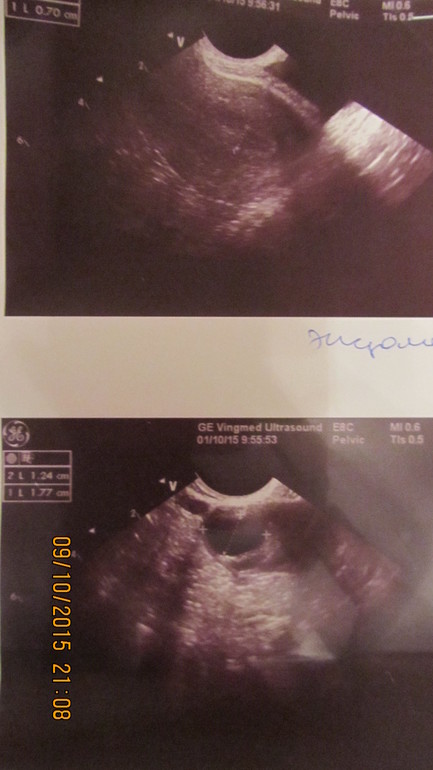

ФолликулометрияДевочки, в этом месяце я делала фолликулометрию. в ПЯ рос ДФ. 5дц - 9 мм, Э - 3,5 мм. 12 дц - 14 мм, Э - 5 мм. 14 дц - 17,7 х 12,5, Э - 7 мм жидкость не опр-ся (фото прилагаю) 19 дц - Э - 10, 7мм, сначала она сказала желтое тело, потом исправила на "Жидкостное образование 17 х 19 мм с геторогенным содержимым. Свободная жидкость в ПМП определяется прослойка - 10 мл (мм?)

сначала она сказала желтое тело, потом исправила на "Жидкостное образование 17 х 19 мм с геторогенным содержимым. Свободная жидкость в ПМП определяется прослойка - 10 мл (мм?)